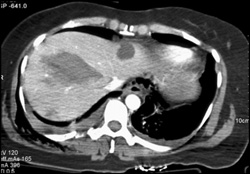

Hepatic Artery- Hepatic Vein Fistulae